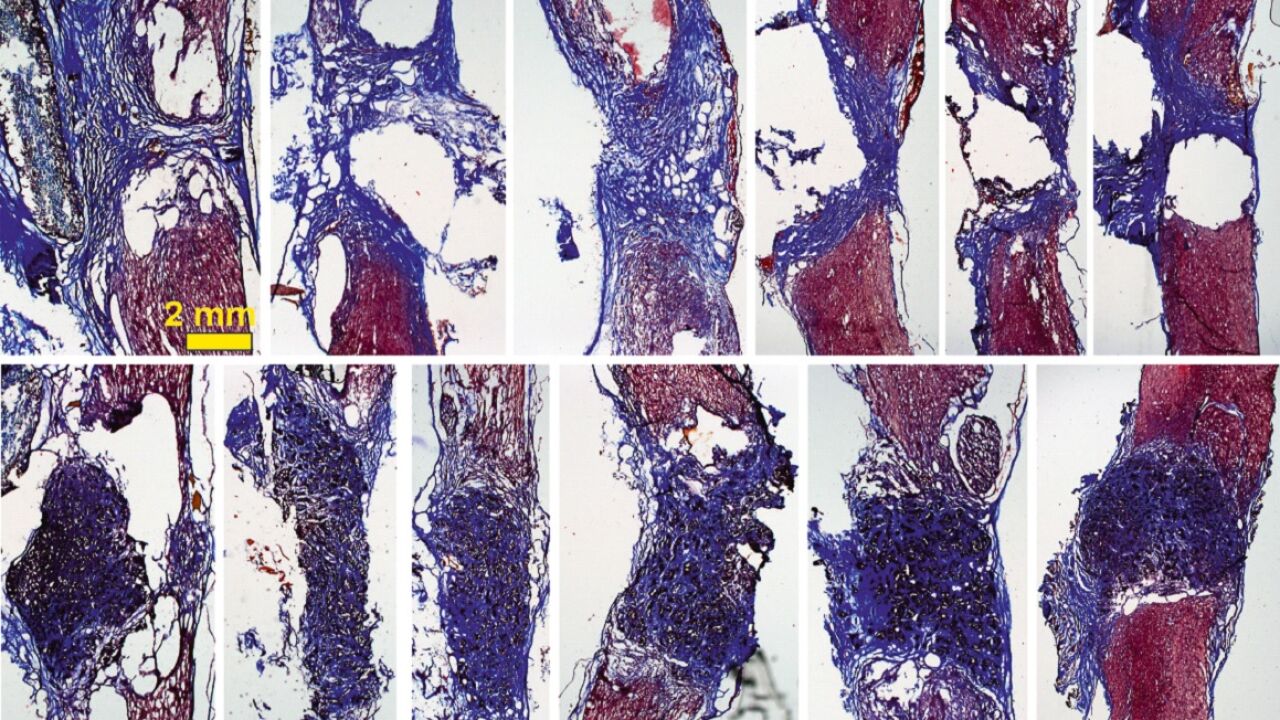

Los tejidos ‘colonizan’ el espacio hueco Sinc

De esta manera, cuando se coloca el scaffold en la médula espinal –en este caso en un modelo de rata con la médula espinal completamente seccionada a nivel torácico–, "vemos que aparecen gran cantidad de vasos sanguíneos, que son fundamentales para nutrir el nuevo tejido, y neuritas (los filamentos que unen unas neuronas con otras)".

La investigadora explica que con esto se observa “cómo las neuronas que han sobrevivido en la zona alrededor de la lesión proyectan sus prolongaciones a través del scaffold y lo invaden en toda su extensión 3D". Todo esto, además, mejora con el tiempo: los resultados son incipientes tras 10 días de implante, pero son mucho más prometedores a los 4 meses.

"Nuestros scaffolds de óxido de grafeno reducido favorecen el crecimiento de vasos sanguíneos más abundantes y más grandes, y neuritas más abundantes, más largas y, además, distribuidas de manera más homogénea en el espacio de la lesión", destaca Serrano.